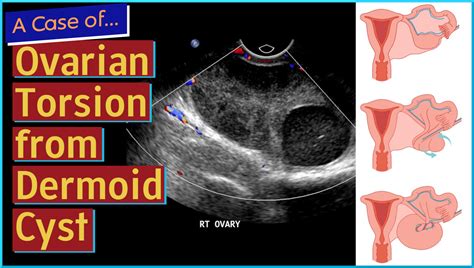

Sudden, sharp pelvic pain is a symptom that should never be ignored, particularly when it presents rapidly. One of the most critical gynecological emergencies that physicians look for when a patient presents with these symptoms is ovarian torsion. This condition occurs when an ovary twists around the ligaments that hold it in place, cutting off its blood supply. Because this is a medical emergency that can lead to permanent damage or loss of the ovary, rapid diagnosis is essential. The primary diagnostic tool utilized in this scenario is an ovarian torsion ultrasound. This imaging modality is the gold standard for evaluating pelvic pain, allowing doctors to visualize the structures within the pelvis and assess the vital blood flow required to save the ovarian tissue.

Several factors increase the risk of developing this condition, most notably the presence of an ovarian cyst or a benign mass, such as a dermoid cyst, which makes the ovary heavy and prone to twisting. During a physical examination, the physician will assess for tenderness, but because the symptoms can be vague, imaging is required to confirm the diagnosis and rule out other potential causes, such as ectopic pregnancy or pelvic inflammatory disease.

Radiologists look for specific markers on the ovarian torsion ultrasound that signal a likely diagnosis. These findings indicate that the ovary is struggling due to compromised blood supply or structural twisting.

The most common finding is an increase in the size of the affected ovary. This occurs because the obstruction of the venous outflow—the veins responsible for carrying blood away from the ovary—leads to congestion, swelling, and edema. Often, the ovary will appear significantly larger than the unaffected contralateral ovary.

Peripheral Displacement of Follicles

In a healthy ovary, follicles are typically distributed throughout the ovarian tissue. When the ovary is enlarged due to edema caused by torsion, the follicles are often pushed to the periphery of the ovary, creating a “string of pearls” appearance. This is a classic sign often noted by ultrasound technicians and radiologists.

Abnormal Blood Flow Patterns

While the absence of flow is the most definitive sign, it is also a late finding. Radiologists look for subtle changes, such as high-resistance flow in the ovarian artery, which suggests the ovary is struggling to receive blood against the pressure of the twist. The presence of a “whirlpool sign”—a twisting of the vascular pedicle—is highly specific for torsion, though it can be technically difficult to visualize.